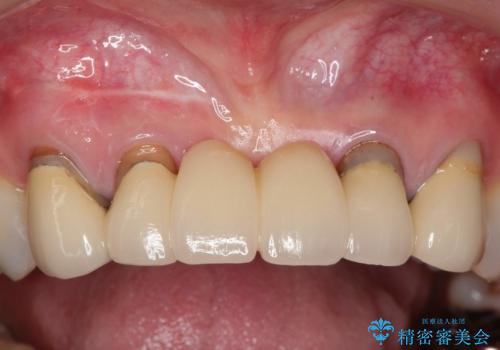

前歯のブリッジの見栄えが悪い→見えないところからしっかりとやり直しを

一見きれいにはいっているセラミックも、はずして中の状態をみるとひどいことが多い。これは、中の土台の状態や処理のクオリティは、短期的には問題を起こしづらく、患者さんには見えない部分だからです。

かぶせ物の種類:PFZ standard